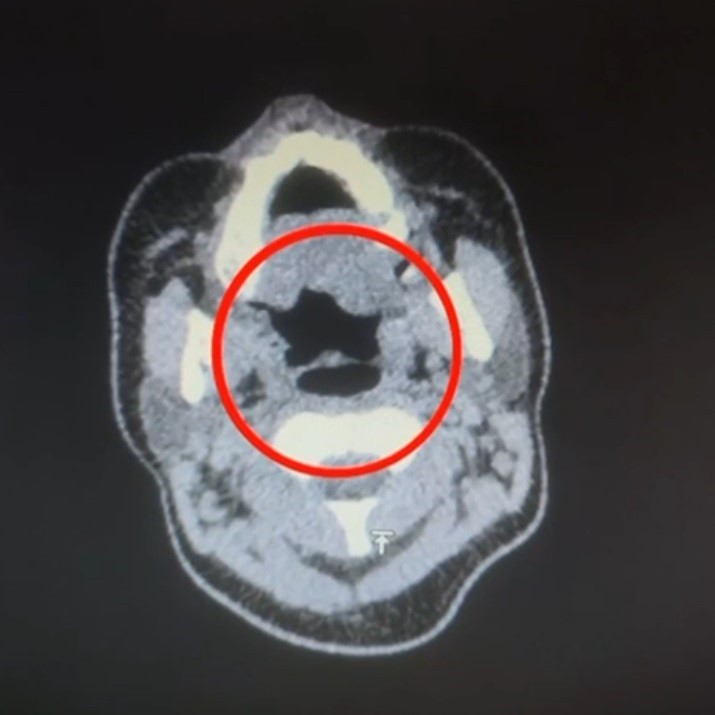

Narkotik Suçlarla Mücadele Şube Müdürlüğü'ne bağlı ekipler, belirlediği hedefe yönelik gerçekleştirdiği operasyonda, A.R. adlı şüpheliyi hastaneye kaldırarak iç beden muayenesi yaptı. Muayene sonucunda, A.R.’nin midesinde toplamda 50 adet kapsül şeklinde 500 gram uyuşturucu madde bulundu.